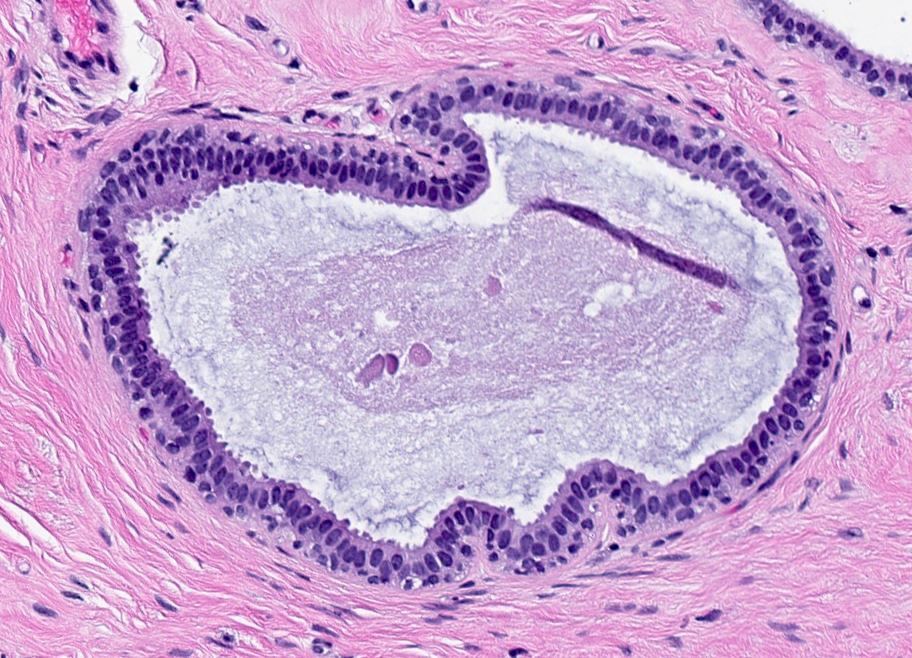

Benign breast cyst

Cyst lined by a single layer of epithelial cells without outer myoepithelial cells. The lumen may contain calcifications (often pale yellow calcium oxalate crystals), secretions, or foamy histiocytes.

Lining may be flat, cuboidal, or undergo columnar change. May even be denuded. Surrounding inflammation/fibrosis is common.